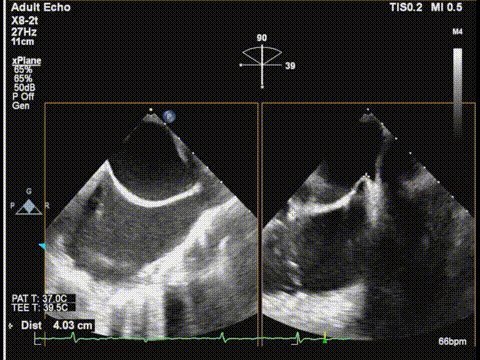

三尖瓣胃底界面

三尖瓣胃底界面color

随后,团队将操作重点转向三尖瓣。在胃底食道超声界面引导下,调整夹合器位置并成功跨瓣,在确保充分捕捉前叶与膈叶后释放夹合器。术后三尖瓣反流明显减轻,遂完全释放夹合器,手术顺利成功。

调整胃底界面评估三尖瓣夹子位置